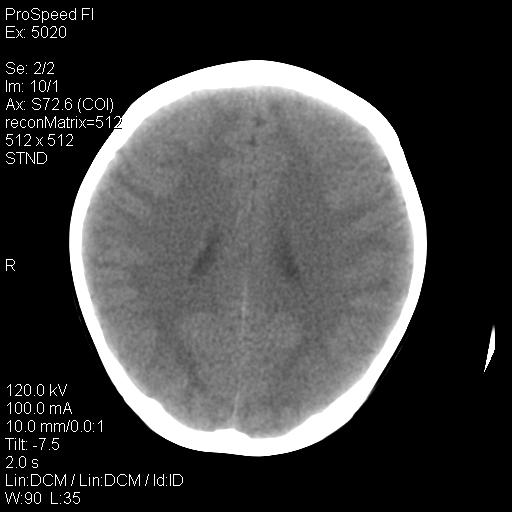

标题: PED1637:M 6Y 顶部无痛性包块两月。 [打印本页]

标题: PED1637:M 6Y 顶部无痛性包块两月。

2、颅骨局部缺失,边缘光滑、整齐

颅骨的病损表现为内外颅骨板层不规则的锋利的破坏,形成“斜边缘”,有一定的特点

颅骨为好发部位,生长缓慢,常位于顶骨、枕骨及颞骨,表现为颅骨缺损,呈圆形或椭圆形,边界清,无硬化

事发冠状缝与矢状缝交界区,密度较低,考虑表皮样囊肿可能性大,其次不除外嗜酸性肉芽肿